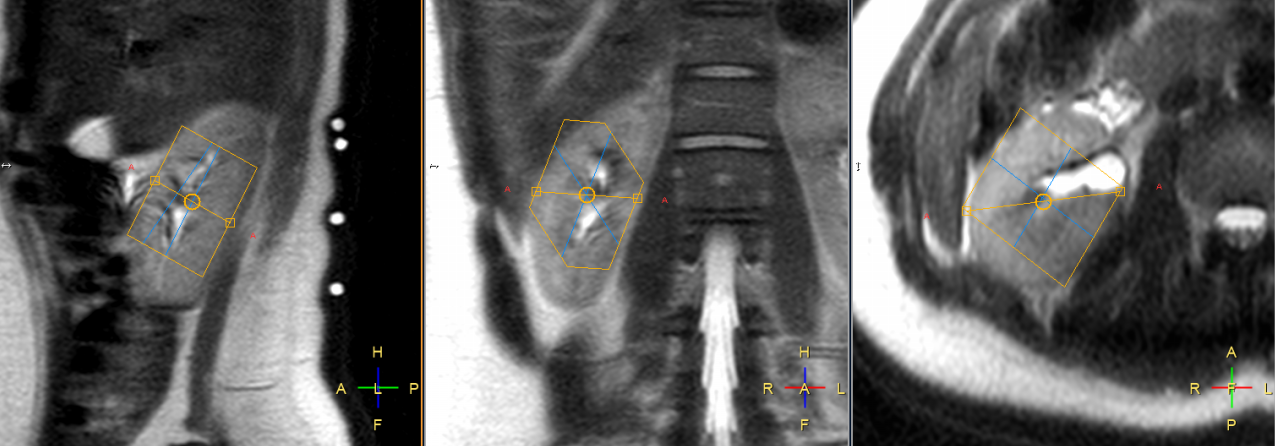

Figure 1: Typical single voxel planning of image guided localized 31P MR spectrum shown on sagittal, coronal and axial planes respectively. The voxel position covered most of the kidney while avoiding the muscle and fat. The four white circles on back of the subject in the sagittal plane (left) represent signals from the vitamin E capsules, used for positioning 31P surface coil.

Single voxel spectra were successfully obtained in all 10 healthy volunteers with a representative voxel position as shown in Figure 1. The voxel position covered most of the kidney while avoiding the muscle and fat to minimize signal contamination from PCr. The averaged 31P MR spectrum of kidneys from 10 healthy volunteers were fitted with AMARES algorithm (Figure 2). Although the acquisition voxel was carefully positioned for each MR spectrum, there was still some PCr contamination from the surrounding muscle due to subject respiration. Spectroscopic data and metabolite ratios were shown in Table 1. The resonance frequency for each metabolite was consistent with the existing literature, while we observed some differences in the reported metabolite ratios.

Image Acquisition and Analysis: All volunteers were examined in the supine position. Several vitamin E capsules were placed on the subject’s back for localizing the kidneys and were then scanned using proton imaging with SShTSE. A 31P surface coil with a diameter of 14 cm was placed underneath the kidney using proton imaging and signal from Vitamin E as reference. Single voxel (typical size of 40 (AP) x 40 (LR) x 60 (FH) mm3) spectra were acquired using ISIS sequence (TR=2500 ms, NSA=1024, sample points=2048, spectral bandwidth=3000 Hz, scan time=45 mins). The acquired spectra were processed with jMRUI [2] software package with following steps: zero filling (4000 zeros), Lorentzian apodization (8 Hz), curve fitting with the AMARES algorithm [3]. The starting values were entered based on preprocessed spectrum and literature results with phosphomonoester (PME) at 7 ppm, inorganic phosphate (Pi) at 5.6 ppm, phosphodiester (PDE) at 3.1 ppm, phospho-creatinine (PCr) at 0.3 ppm, adenosine triphosphate-γ (ATP-γ) at -2.3 ppm, ATP- α at -7.4 ppm and ATP-β at -15.7 ppm. AMARES algorithm calculated the final intensities and positions of the individual peaks. For further evaluation, the following metabolite ratios were calculated based on their areas under the curve (AUC): PME/ Pi, PME/PDE, PDE/Pi, PME/ATP-α, PDE/ATP-α, PME/ATP-β, and ATP-γ/ATP-α.